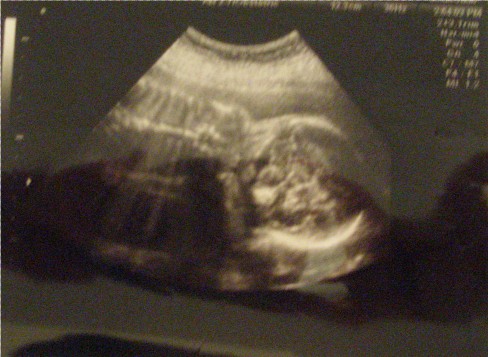

As for the baby, she couldn't be more perfect. My OB said she was measuring perfectly and her heartbeat is strong. Physically, this has been a rather uneventful pregnancy and I am very grateful.

I'll post pictures later but they make Ed-lie look like a lizard.

PICS of the lizard:

oh you have my lizard baby!!

my little is always sleeping face down like that... so cute

Seriously, her nose was so much cuter the last time. Im going to say she wasn't as cooperative this time and maybe when I go for my GTT next week, I can sneak in another sono and figure out if I need to start saving for college or rhinoplasty.